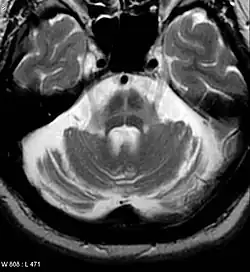

Both MRI and CT scanning may show a decrease in the size of the cerebellum and pons in those with cerebellar features (MSA-C). The putamen is hypointense on T2-weighted MRI and may show an increased deposition of iron in the Parkinsonian (MSA-P) form. In MSA-C, a "hot cross bun" sign is sometimes found; it reflects atrophy of the pontocerebellar tracts that give T2 hyper intense signal intensity in the atrophic pons.

MRI changes are not required to diagnose the disease as these features are often absent, especially early in the course of the disease. Additionally, the changes can be quite subtle and are usually missed by examiners who are not experienced with MSA.